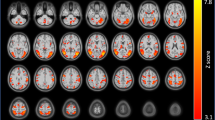

Monetary incentive delay task

A main effect of anticipation for all four of the factorial analyses replicated previous findings from the literature and revealed significant clusters in regions including striatum, insula, thalamus, and medial wall premotor regions (Fig. S2, N = 18 rTMS, N = 21 sham, per-voxel P = 0.002, cluster size threshold = 11). However, no significant group nor group × stimuli interaction effects were observed. Activation peaks for each factorial analysis are presented in Table S3.

Negative-affect picture processing

A main effect of stimulus across groups revealed significantly increased activity in several regions including the insular cortex bilaterally to face pictures, and increased activity in the lingual gyrus to pictures from The International Affective Picture System (IAPS) (Fig. S3 and Table S4, N = 17 rTMS, N = 21 sham, per-voxel P = 0.002, cluster size threshold = 11). No significant group nor stimuli × group interactions were identified. A 2 × 2 ANOVA on the extracted β values in the insula confirmed a significant main effect of stimulus [left anterior insula: F(1, 36) = 31.90, P < 0.001, η2p = 0.47; right anterior insula: F(1, 36) = 32.23, P < 0.001, η2p = 0.47], driven by face pictures (left anterior insula: t = −5.57, P < 0.001; right anterior insula: t = −5.58, P < 0.001), and a non-significant stimuli × group interaction (Ps > 0.2).

Alcohol beverage picture processing

Alcohol pictures compared to non-alcohol pictures activated significantly more the visual cortex (MNI 4, −83, −5) and left precuneus (MNI −14, −89, 4) (per-voxel P = 0.002, cluster size threshold = 12). However, the 2 × 2 ANOVA showed no significant group and stimuli × group interaction (N = 18 rTMS, N = 20 sham).